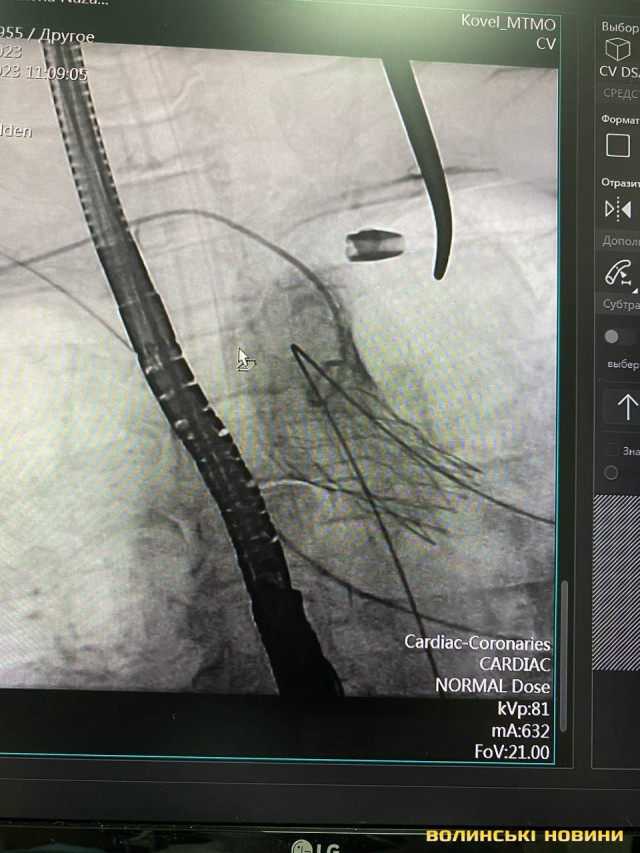

Лікарі Центру дитячої кардіології та кардіохірургії (м. Київ) спільно зі спеціалістами Ковельського МТМО виконали процедуру TAVI – транскатетерну заміну аортальна клапана.

Лікарі замінили аортальний клапан без зупинки серця через 3-х сантиметровий розріз. Тривалість операції на серці склала 2 години.

«Нашій пацієнтці 68 років, вона страждала від критичного стенозу аортального клапана – вади серця, при якій один із основних клапанів майже не відкривається. Але зараз вона в стабільному стані і тепер попереду в неї здорове та повноцінне життя», – розповів завідувач кардіохірургічного центру Володимир Танський.

Знімок клапана уже в серці